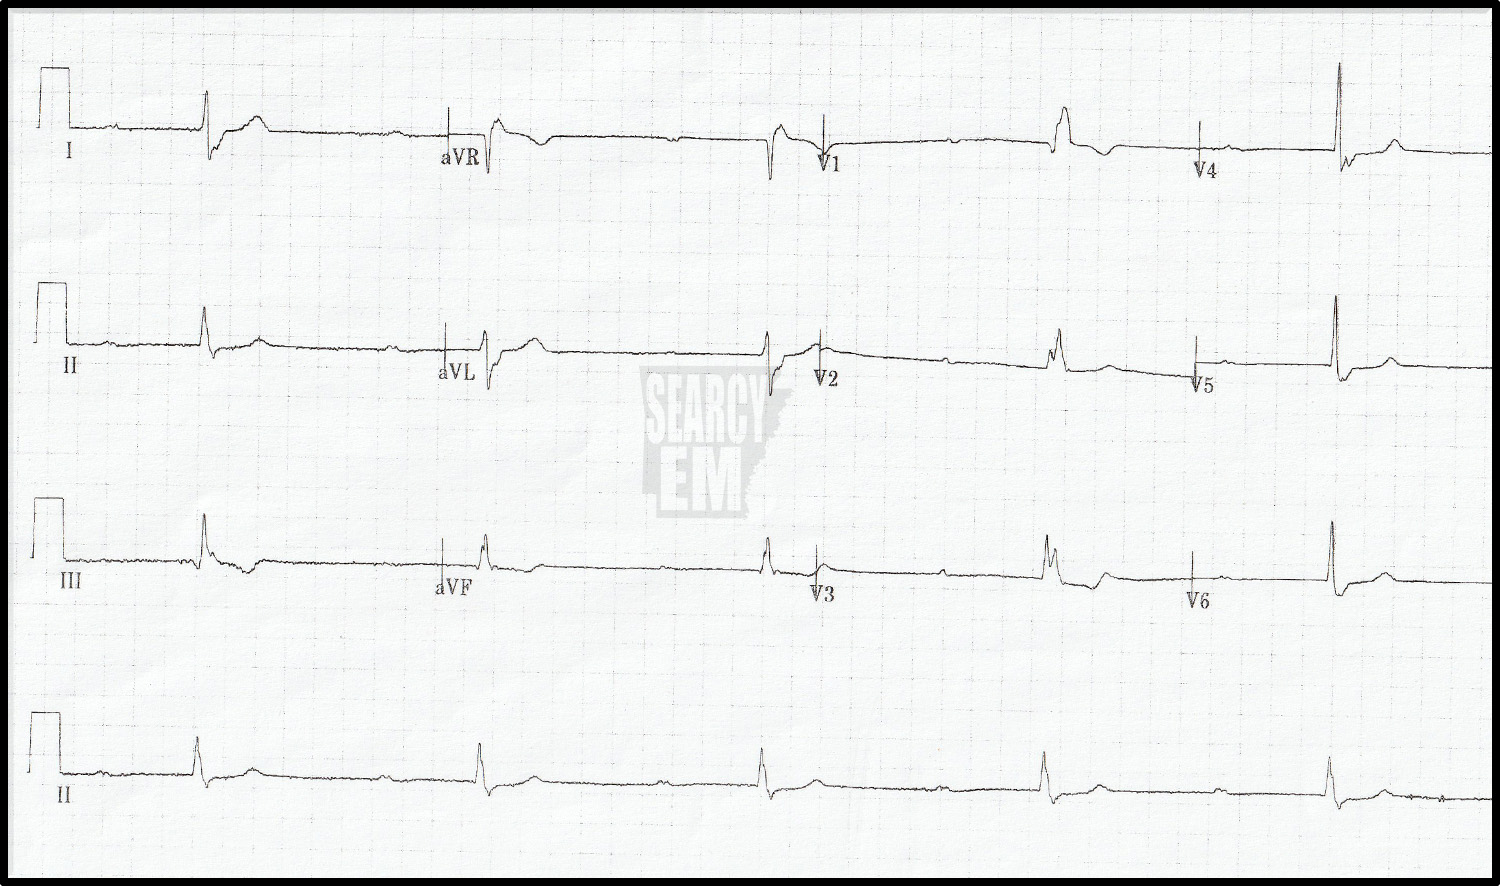

57 Interpretation

Sinus with ST depression in the anterior leads. Concerning for anterior ischemia vs posterior infarction.

The same patient as EKG 57. In this tracing, leads V4, V5, and V6 have been moved to positions V7, V8, and V9. The depression remains in the anterior leads (V2, V3), but now we see ST elevation in leads V7-V9). This is a posterior STEMI. You can see that the leads 7, 8, and 9 were hand written in on the tracing as the machine does not know that the leads were moved.